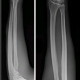

Ada pasien laki-laki berusia 32 tahun datang ke IGD dengan keluhan nyeri pada lengannya. Pasien bercerita bahwa di habis ikut tawuran, lalu tidak sengaja lengan terpukul dengan besi. Berdasarkan gambar rontgen, apa fraktur yang terjadi pada pasien?

Jawabannya Nightstick Fracture, ya dok. Fraktur linear pada tulang ulna biasanya terjadi akibat mekanisme pukulan langsung ke lengan bawah. Ini biasanya merupakan cedera defensif yang terjadi pada orang yang berusaha memproteksi kepalanya dari pukulan seperti tongkat polisi. Nightstick Fracture dengan minimal displacement atau angulasi seperti gambar pada rontgen, dapat di tata laksan dengan gips lengan bawah (slab tangan hingga atas siku tangan ). Sedangkan, fraktur monteggia adalah cedera lebih kompleks yang melibatkan fraktur ulna dan dislokasi caput radial.